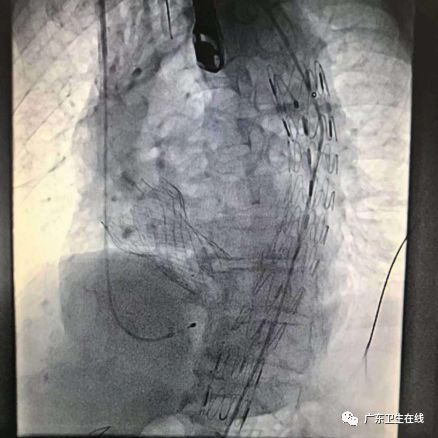

▲TAVR+TEVAR 影像